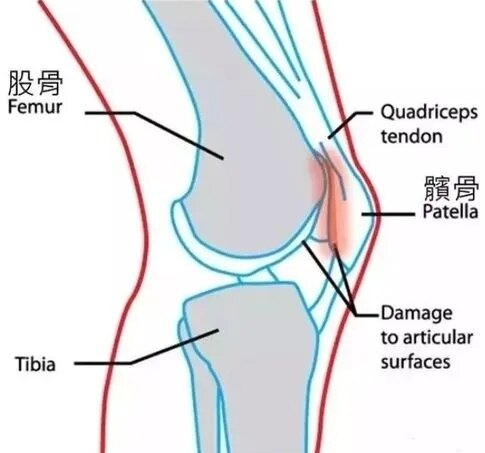

股骨、胫骨、腓骨、髌骨共同构成膝关节的骨结构。在膝关节前方游离,扁栗状,神一般存在的那个就是髌骨。北方称膝盖骨或波棱盖。还有人称其为迎面骨。医学上它是人体最大的一颗籽骨。

那么偏外,会出现什么问题呢?最典型的,就是上下楼疼痛,下蹲困难。严重的平底走路都费劲。主要是,匹配不好,局部压强大,磨损所致。